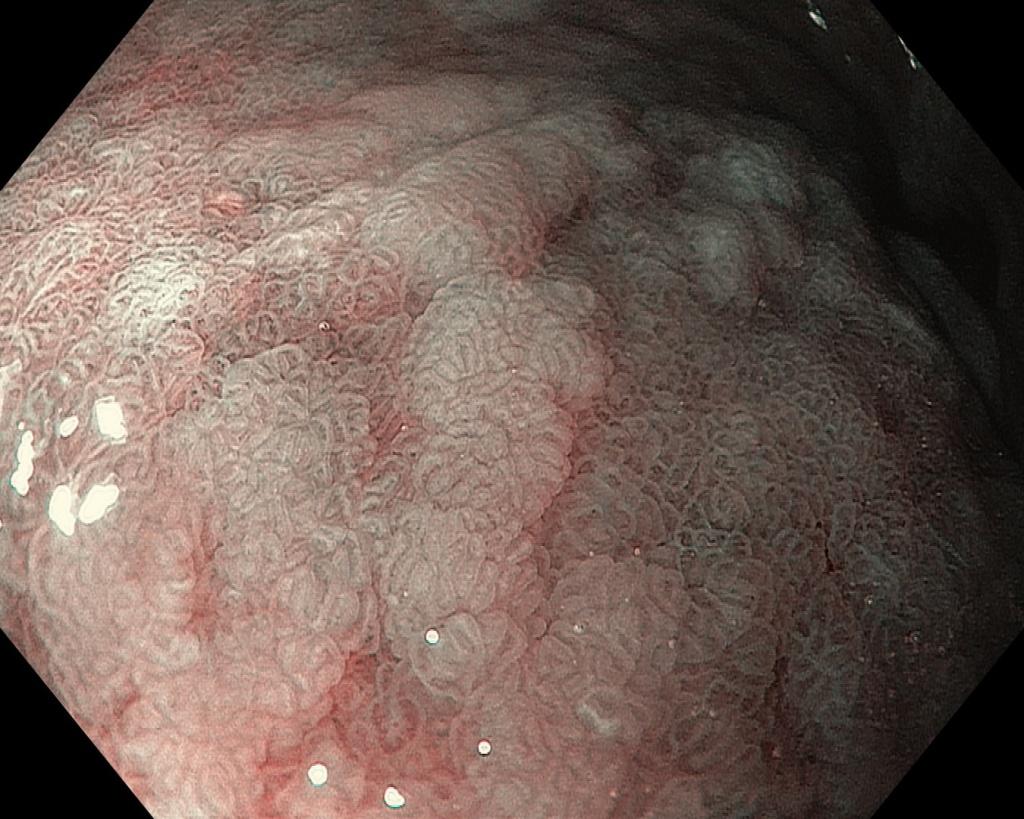

Кишечная метаплазия